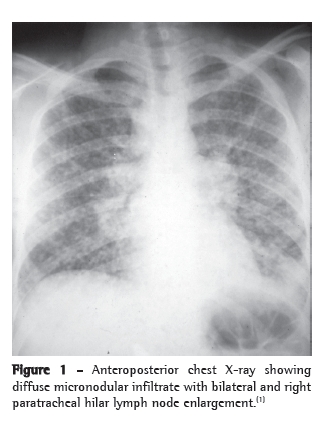

Radiological tests are not specific for histoplasmosis. In acute pulmonary histoplasmosis, the most common radiological finding is the presence of bilateral and mediastinal hilar lymph node enlargement associated with bilateral perihilar reticulonodular infiltrate (Figure 1). However, unilateral hilar lymph node enlargement, diffuse reticulonodular interstitial infiltrate, cavitation and diffuse or isolated nodules can be found. In chronic pulmonary histoplasmosis, the radiological findings are similar to those in adult or reinfection tuberculosis, that is, progressive infiltrate in the upper lobe, cavitation and signs of fibrosis. Mediastinal enlargement can be seen principally on CT scans of the chest of patients with granulomatous histoplasmosis and mediastinal fibrosis. The presence of a solitary nodule or multiple nodules with central calcification is quite characteristic of the nodular form, that is, of histoplasmoma.(1-5)